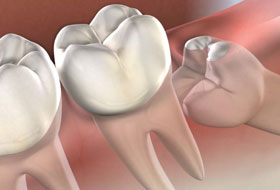

Wisdom teeth generally erupt into the mouth by the age of 18 years and may even extend upto 22 years or even later. They may erupt into the oral cavity depending on the space available or may remain in the bone unerupted. Their eruption into the oral cavity depends on many factors like the space available, the position of the tooth, early shedding of the other teeth.